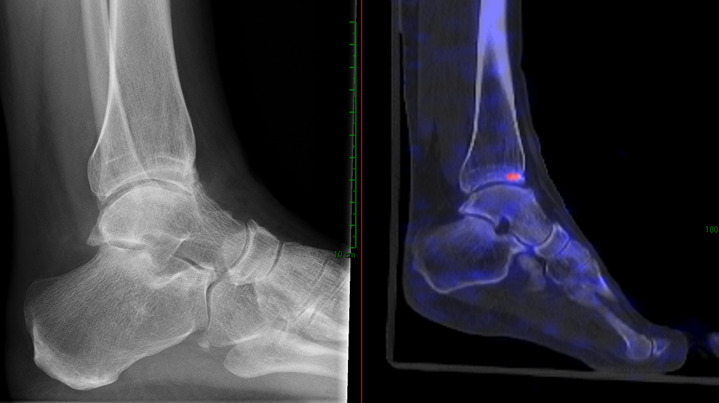

Abstract Image